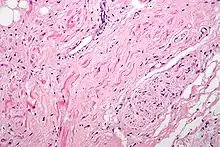

Section of the neck at about the level of the sixth cervical vertebra